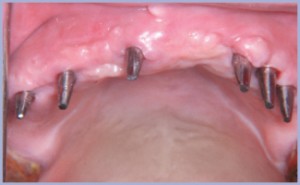

L’esame ortopanoramico (fig. 17) metteva in evidenza una discreta quantità di osso disponibile nel settore mascellare anteriore per cui si decideva per l’inserimento di 6 impianti. Lo scarso spessore vestibolo orale dell’osso residuo richiedeva tecniche espansive per l’inserimento degli impianti (fig. 18), tutti di diametro 3,3 mm. L’esame ortopanoramico (fig. 19), eseguito a 6 mesi dal posizionamento implantare, metteva in evidenza l’integrazione degli impianti confermata clinicamente al momento della seconda fase chirurgica (figg. 20, 21).

Al momento della consegna i tessuti molli presentavano un buon grado di maturazione nonostante fossero trascorse solo due settimane dalla seconda fase chirurgica (figg. 26, 27, 28).